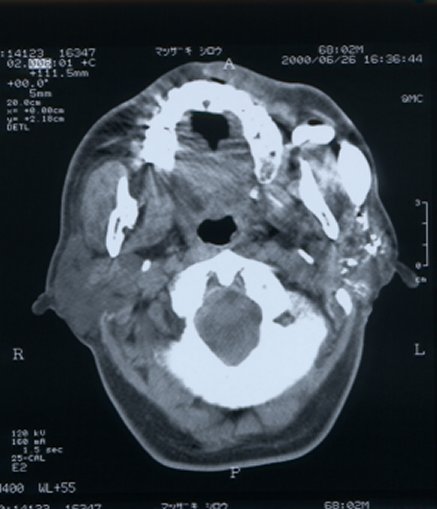

*Legend: Male, 68 years. He's noticed a chronic painless swelling

on the l-buccal region for decades of life. He has applied a pressure over

it to get relief. CT sialograms revealed Stenon's duct had two large diverticula.